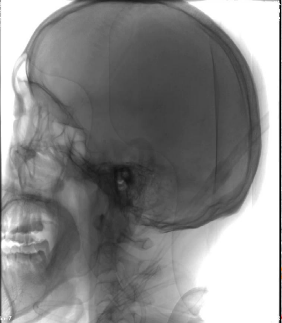

左侧椎动脉起始部成形

病历夹什么径技·第152期|串联营病历夹:川陕大营_https://www.jmylbn.com_新闻资讯_第21张

病历夹什么径技·第152期|串联营病历夹:川陕大营_https://www.jmylbn.com_新闻资讯_第22张

<<滑动查看下一张图片>>

确认血栓远近端

病历夹什么径技·第152期|串联营病历夹:川陕大营_https://www.jmylbn.com_新闻资讯_第23张

血管再通后造影

病历夹什么径技·第152期|串联营病历夹:川陕大营_https://www.jmylbn.com_新闻资讯_第24张

血管再通及左椎支架植入

病历夹什么径技·第152期|串联营病历夹:川陕大营_https://www.jmylbn.com_新闻资讯_第25张

病历夹什么径技·第152期|串联营病历夹:川陕大营_https://www.jmylbn.com_新闻资讯_第26张

病历夹什么径技·第152期|串联营病历夹:川陕大营_https://www.jmylbn.com_新闻资讯_第27张

左椎支架植入后造影